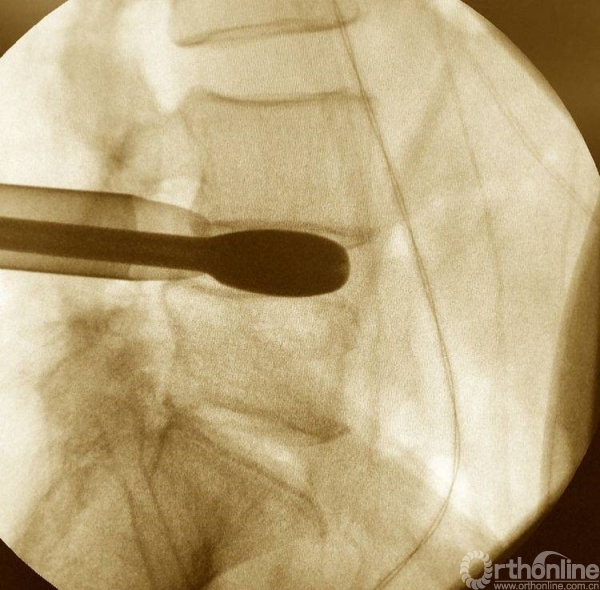

消毒前,给予椎间隙定位

按照定位标志,画出L4-L5椎弓根位置,为零透视下椎管减压做准备

术前透视标记出棘突椎板关节突关节、椎弓根、横突复合体螺钉进钉路线的正位透视片

放入减压工作通道

处理干净椎间隙后,透视观察工作通道的位置,镜下看到前纵韧带的纤维交错位置,为减压充分标志